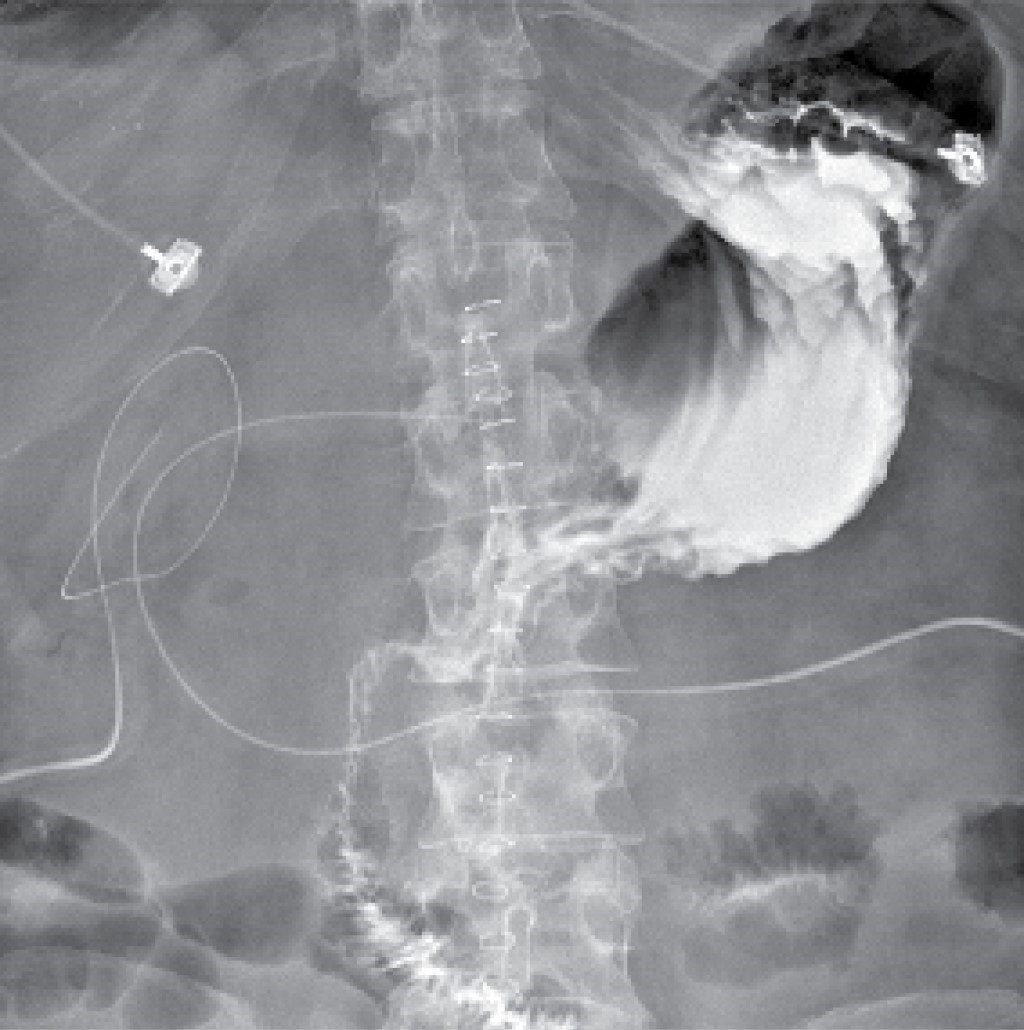

During the approach, laboratory tests were performed (Table 1), and a double contrast abdominal tomography (Figure 1), in which the outflow of contrast material into the abdominal cavity at the level of the first portion of the duodenum and much free air, was evident.

Figure 1